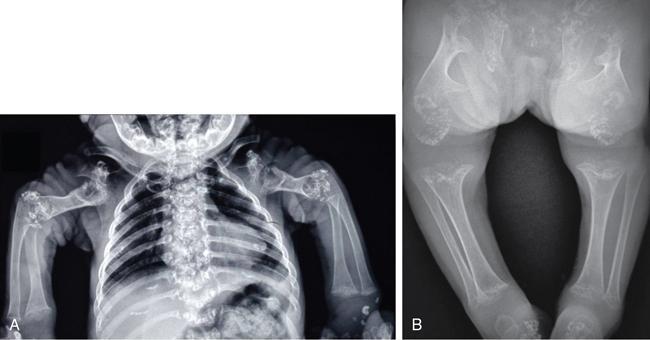

MISCELLANEOUS PAEDIATRIC RADIOGRAPHY – TECHNIQUES AND INTERPRETATION: SKELETAL SURVEY Padma V. Badhe The skeletal survey, generally performed in children, is a set of radiographs done in order to evaluate the entire skeleton. A skeletal survey, commonly used to evaluate skeletal dysplasias, acquired metabolic disorders and suspected child abuse, is still the key radiological investigation for the same. Hence, an explicit understanding of the technique along with the common disorders forms the basis of making a diagnosis in these paediatric pathologies. A skeletal survey is done for various skeletal dysplasias, non-accidental injury (battered baby syndrome) and suspected child abuse. It can also be done in cases of metabolic bone diseases, disseminated infections, multiple myeloma, eosinophilic granuloma. It is also used in evaluation of metastatic bone diseases and polyarticular arthropathy. Orthogonal views of the skull, spine, pelvis and one extremity are taken, preferable in standing position. For preterm babies/newborns, AP and lateral views of babygram may be taken. Projections: For skeletal dysplasias: Additional views: Both extremities may be taken if epiphyseal abnormalities and limb asymmetry is present. Focused views for specific pathologies may be taken. When a diagnosis remains uncertain, 1 year follow up is usually recommended. For preterm babies/newborns: AP and lateral views of babygram may be taken with additional specific views for extremities. For suspected non-accidental injury (NAI): AP and oblique view of chest is taken for better evaluation of the ribs. AP view of abdomen with pelvis. Both upper and lower limbs are evaluated. In lower limbs, two projections in AP and lateral (one with both femur including hip and knee joints; and another for foot and ankle) is taken. AP and lateral views of whole spine, skull. Oblique view of hands. A babygram should be avoided in cases of NAI, as subtle fractures are easily missed. Proper legal documentation while taking the views is very important and ideally two health care professionals must be present. For metabolic disorders: entire skeletal survey is usually not required. Specific views of hands, knees and spine may be taken with additional views depending on the suspected pathology. Centring point: Varies according to the part being examined. Angulation, collimation and orientation: Varies according to the part being examined. Images must be well collimated to obtain lower radiation dose. Detector size: Varies according to the part being examined: 8″ × 10″, 10″ × 12″, 11″ × 14″. Exposure: Ideally high kVp images are taken to reduce radiation dose. But in suspected NAI, low kVp/high mA images are recommended to better demonstrate findings. SID (Source Image Distance):100 cm Grid: Grids are not routinely used to image spine, pelvis, skull and abdomen in children. Radiation dosage: 0.3–3 mSv Essential image characteristics: Adequate spatial resolution, high signal to noise ratio, low kVp (50–70) for high contrast should be done. Excellent bone and soft tissue details are required. The presentation of skeletal dysplasia can range anywhere from minimal stunting of growth and bowing of limbs to severe dwarfism and multiple fractures. Knowledge of the commonly encountered dysplasias with an approach to arrive at a diagnosis is vital in any Radiologist’s practice The following flow chart summarizes the classification of important skeletal dysplasia: The following table summarizes the various dysplasias affecting the axial skeleton: TABLE 7.5.1.1 The following flow chart summarizes the working approach to skeletal dysplasias: Osteopetrosis (Albers-Schonberg disease/Marble bone disease) (Fig 7.5.1.1): Osteopetrosis clinically presents with anaemia/thrombocytopenia or cranial nerve compression. Radiological features include generalized increase in bone density with loss of medullary space. However, cortico-medullary appreciation with cortical thinning is also rarely seen. Bone within bone appearance with Erlenmeyer flask deformity is also noted. Pyknodysostosis (Figs. 7.5.1.2 and 7.5.1.3): patient presents with short stature. Unlike osteopetrosis, there is no anaemia. Radiographs show generalized increase in bone density with preserved medullary canal. There is mandibular hypoplasia with obtuse angle. Acro-osteolysis is also a feature. Dental caries with osteomyelitis of the jaw may be seen. Sclerosing dysplasia presenting as wavy undulating new bone formation. Usually monomelic, lower limb and along one side. The classic appearance is described as Dripping candle Wax sign. It is a Sclerosing dysplasia with radiological features of symmetric juxta-articular involvement in epimetaphyseal region. They are 1–10 mm in diameter and uniform in size. No metabolic activity is seen on bone scans. This skeletal dysplasia shows diffuse decrease in bone density with paper-thin cortex. Fractures heal in normal time but shows callus with poorly cellular matrix. Wormian bones and enlarged sinuses may be seen. Codfish vertebra (Biconcave vertebra) may be seen. Metaphyseal corner fractures are not seen in osteogenesis imperfecta that helps to differentiate it from battered baby syndrome. There are four types of OI out of which type one is most common (Figs. 7.5.1.6 and 7.5.1.7). The radiological features of MPS include Osteopenia and Universal platyspondyly. The intervertebral disc spaces are maintained. Proximal pointed metacarpals is an important radiological finding. Hurler’s syndrome show anteroinferior beaking with short and wide metacarpals. Varus deformity of humerus is characteristically seen in Hurler’s syndrome (Fig. 7.5.1.8). Mental retardation & corneal clouding is seen in Hurler’s syndrome whereas these Hunter’s disease has normal intelligence with no corneal clouding. Morquio’s syndrome shows central beaking (Fig 7.5.1.9). This skeletal dysplasia shows normal bone density with rhizomelic limb shortening and normal trunk. Narrowing of spinal canal is classically seen with decrease in the Interpedicular distance caudally. Other radiological features include trident hand (separation of middle & third fingers), Champagne glass pelvis (short, flat ilia and small sciatic notch), bullet nose vertebra and overexpansion of skull with narrow foramen magnum (Fig. 7.5.1.10). This skeletal dysplasia is characterized by normal bone density with dwarfism and normal craniofacial skeleton. The interpedicular distance is normal. There is severe platyspondyly with anterior tonguing (disappears at older age). Other radiological features include increased disc space, short stubby metacarpals, small irregular epiphysis and widened metaphysis. Anterior tonguing is a feature of Pseudoachondroplasia. This form of skeletal dysplasia involves the spine and epiphyses (Fig. 7.5.1.11). There is normal bone density with rhizomelia. Spine and Pelvis can be involved. Premature osteoarthritis can be seen. The other characteristic features include Platyspondyly and small irregular epiphysis. There are two forms Spondyloepiphyseal dysplasia Congenital and Spondyloepiphyseal dysplasia Tarda. Spondyloepiphyseal dysplasia Congenita is Autosomal dominant and shows pear-shaped vertebrae. Spondyloepiphyseal dysplasia Tarda is X Linked recessive with heaped up vertebrae. It has two forms. The first form is Conradi Hunermann syndrome which is autosomal dominant characterized by asymmetric limb shortening with metaphyseal flaring (Fig. 7.5.1.12). The Autosomal recessive form is Fatal in first few years. Rickets: Rickets refers to deficient mineralization of the growth plate in the paediatric population due to deficiency of vitamin D. In an immature skeleton, there is abnormal mineralization at the zone of provisional calcification in the metaphysis due to osteoid deposition resulting in widening of the growth plate. The features of rickets include fraying, splaying and cupping (Fig. 7.5.1.13). Fraying denotes indistinct margins of the metaphysis whereas splaying denotes widening of metaphyseal ends. Term ‘Cupping’ is used for increased concavity of the metaphysis. These findings are typically seen involving areas of active growth (e.g. distal femur and proximal tibia in the knee) Bowing is a result of associated osteomalacia leading to weakening of weight-bearing lower limb bones. Other bone deformities such as genu valga, genu varum, protrusio acetabuli can also be seen. The lower ribs may also be drawn inwards inferiorly by the attachment of the diaphragm this is called Harrison’s sulcus. Scurvy: Scurvy is a result of dietary deficiency of Vitamin C (ascorbic acid). The classic presentation is that of a patient with an increased bleeding tendency and osteopenia with poor wound healing. Features of scurvy include generalized osteopenia with cortical thinning termed as ‘pencil-point’ cortex. Other radiological findings include the periosteal reaction due to subperiosteal haemorrhage. Expansion of the costochondral junctions occurs forming scorbutic rosary. Bleeding into the joint spaces may result in hemarthrosis. Circular, opaque radiologic shadow surrounding epiphyseal centres of ossification may result from bleeding (Wimberger ring sign) (Fig. 7.5.1.14). Frankel line may be seen. It represents dense zone of provisional calcification. Lucent metaphyseal band is seen underlying Frankel line called as Trümmerfeld zone. Metaphyseal spurs may be seen that result in cupping of the metaphysis (Pelkin spur). Pelkin fracture (metaphyseal corner fracture) can also be seen. Images obtained must be of good resolution with adequate bone and soft tissue details. Additional views: They have already been described in positioning. CT Brain in can be done in cases of NAI to look for subdural hematomas. A skeletal survey is the first-line imaging modality for evaluation of skeletal dysplasia, nonaccidental injury and metabolic bone diseases. The skeletal survey must be tailored according to the respective indication. It helps to characterize syndromic patterns in skeletal dysplasias, with evaluation of complications. In cases of diagnostic dilemmas, additional focused view and occasionally yearly follow-up is recommended. A high index of suspicion is needed in utilizing skeletal survey as a diagnostic modality in NAI. At the same time, one must also remember the legal and social implications of making this diagnosis. BABYGRAM Babygram is a colloquial term used for a radiograph of the whole body of a newborn or just the chest and abdomen (thoracoabdominal babygram) on a single image. As the name suggests it is a rather non-targeted study. It is most commonly requested after line placement. Evaluation of skeletal abnormalities in a deceased foetus is typically performed using anteroposterior and lateral views of a babygram. It helps in pointing out skeletal causes of death in stillborn or dead foetuses. This will help the treating physician and parents understand the reason for baby’s death. This will also help in future genetic counselling of the couple. Sometimes chest or abdominal radiographs of the baby are requested but due to radiographers error or inexperience with small babies, there is inclusion of the region not to be assessed leading to a false babygram. Babygram is most frequently done after line placement in neonates, to view the position of the umbilical vein or artery catheter and to confirm appropriate placement. It is a useful modality in skeletal dysplasias (Fig. 7.5.1.15) like osteogenesis imperfecta, thanatophoric dysplasia and chondrodysplasia punctata. It can also be used for skeletal deformations probably caused by foetus akinesia and in cases of Caudal regression syndrome. In stillborn foetuses, it is used for evaluation of skeletal dysplasias prior to an autopsy (Fig. 7.5.1.16). It is also used in screening for surfactant deficiency and in cases of Necrotizing Enterocolitis in preterm babies where it can help to see the bowel dilatation, intramural and portal venous gas. It can be done in aneuploidies like trisomy 18 and in cases of sudden infantile death syndrome. All the essential equipment and room need to be prepared including the exposure factor. This should be done prior to placing the baby on the table to prevent any neonatal heat loss. Ensure that the baby is correctly identified. Give brief explanation to the patient’s parents regarding the procedure, its risks and benefits. Ensure that the accompanying relative is not pregnant (if female). Parents/guardians/nurses should be instructed to hold the baby with arms above the head and legs straight down. Sandbags/tapes can be used to immobilize the baby. Avoid taking the radiograph when baby is crying. Normal appearance: The endotracheal tube should lie in the lower third of trachea, distance can vary with position of baby’s head. Umbilical artery catheter has an inferior dip along the internal iliac artery, which then turns superiorly along the aorta. The tip should lie in the mid-thoracic aorta (T6–T10) or lower (L3–L4) away from aortic branches to prevent any thrombosis. Umbilical venous catheter does not have the inferior curvature, but rather a posterolateral angulation to the right near the liver through the ductus venosus. The tip should lie in the superior IVC or right atrium at T8/T9 vertebral level (Fig. 7.5.1.17). Portal venous gas may be seen initially after insertion. In a stillborn foetus, the approximate gestation age of the foetus and corresponding ossification centres must be known. In early gestation, the lack of appearance of an ossification centre may be mistaken for skeletal dysplasia. Both chest and abdomen should be included. In a rotated patient, the distance between the spinous process to medial end of clavicles will be asymmetric. The medial end of clavicle should overlap the lung apex, if above, suggests lordotic image. Motion artefacts to be reduced as much as possible. A crying neonate may result in an expiratory film, and hence must be evaluated accordingly. In evaluation of skeletal dysplasias in the newborn, additional views of skull and hand have to be obtained. Baby gram is a useful diagnostic investigation for position of the paediatric umbilical catheters. It helps in general survey in skeletal dysplasia (Fig. 7.5.1.18). It is a simple, effective study in deceased foetus for diagnosis and further counselling, sometimes obviating the need for an autopsy. As baby gram is a non-targeted study, it increases the dose of radiation for the baby. As the exposure settings remain same for the entire body of the baby, the quality of the image decreases. This increases the chances of missing subtle findings. The babygram in a neonate is currently used to localize umbilical catheters. In stillborn fetuses, it is still an important study for documenting and confirming skeletal dysplasias. Understanding the normal appearance as per gestation age and patterns of various common skeletal dysplasias is essential for evaluation. Being a non-targeted study, it should not be used as an alternative study to evaluate the chest or abdomen considering radiation exposure and poorer image quality. INVERTOGRAM Invertogram was first described by Wangensteen and Rice in 1930. It was used as a first investigation to be ordered in evaluation of infants with clinically diagnosed or suspected Anorectal Malformation (ARM). ARM is a serious but surgically treatable congenital malformation with approximate incidence of 1 in 5000 live births. Though the diagnosis of this condition is based on clinical history and physical examination, imaging plays an important role in deciding the type of ARM, and associated complications to aid in management. International classification of anorectal malformations is as follows. Syndromic association is seen as a part of VACTERL defects, trisomy 21 13 and 18, Klippel Feil syndrome, cat eye syndrome etc. The main indication of Invertogram is to evaluate anorectal malformation in a neonate. A radio-opaque marker is placed over the external anal opening. Infant is held inverted by holding both thighs, maintaining this posture for at least 5 minutes before taking an X-ray in true lateral position (Fig. 7.5.1.19). Exposure is made during inspiration. The Invertogram should ideally be done 24 hours after birth as, the rectal gas may not reach the terminal segment if study is done too early. Pubo-coccygeal line (PCL) is drawn from upper border of pubic symphysis (which corresponds to centre of pubic bone on lateral X-ray) to sacrococcygeal junction. I point is the inferior most point of ischial ossification centre. A line which is drawn parallel to PC line passing through the I point is called I line. ‘A’ point is represented by marker placed at anal pit. The position of rectal pouch gas shadow is observed with respect to these lines and appropriate diagnosis is made (Fig. 7.5.1.21). A diagnosis of high ARM is made when gas shadow of rectal pouch is cranial to PCL. If rectal pouch gas shadow is in between PCL and I line, it is called as intermediate ARM and if it is caudal to I line, it is diagnosed as low ARM. Gas in urinary bladder or vagina or beaking of gas shadow of rectal pouch indicates fistula into one of these sites. Associated congenital abnormalities like spinal defects are also looked for in the invertogram (Fig. 7.5.1.22). Invertogram done too early (less than 24 hours) may not demonstrate rectal gas. Meconium plugging the terminal segment gives false position of the rectal gas. Positioning can cause discomfort to child and an irritated crying child actively contracts the sphincter muscles, pushing the gas shadow higher. Rectum may be pulled cephalad due to gravity in inverted position. The rectal gas may escape through an associated fistula. Erroneous interpretation can also occur due to sacral anomalies and when gas in vaginal cavity is misinterpreted as distal rectal gas. Both ischial bones should superimpose and terminal blind loop should be well distended. It is an easily available modality and can be done quickly, does not require additional equipment. It has lesser radiation dose as compared to CT invertogram. It provides a rough guide as to the type of ARM and decides management. Higher localization of obstruction due to various causes like meconium plugging, imaging done too early etc. as described above in pitfalls. It is more uncomfortable to the baby as compared to the prone cross-table lateral view, and a crying baby contracts the puborectalis leading to erroneous results. K. L. Narasimharao et al. modified the technique and proposed cross-table lateral view for evaluation of infants with ARM’s which has shown equal or better information and has now replaced invertogram (Fig. 7.5.1.23). Prone cross-table lateral view is considered equivalent or even better in determining the level of anomaly. Positioning is in this view is prone in genupectoral position (at least for 3 minutes). It is taken in true lateral and during inspiration. The lines used to delineate types of ARM is essentially the same as in an invertogram. It is preferred over invertogram as relatively easy positioning of the infant and less discomfort allows for better cooperation of neonate during the study. It also eliminates the effect of gravity. ARM with fistula is better delineated as, in an invertogram, fistula/gas is at the highest level and gas may escape through it. CT invertogram is another modality that delineates anatomy better but is rarely used. In the era of cross-section imaging, MRI and USG have opened new modalities for accurate diagnosis of ARM, but invertogram being readily available, inexpensive, quick and cost-effective is used as first investigation for evaluating a patient with suspected or confirmed case of ARM. Cross-table lateral view has replaced invertograms as it is more patient-friendly and equally effective. UPPER GASTROINTESTINAL SERIES Rushit S. Shah An upper gastrointestinal (GI) study is a radiographic examination of the GI tract from the pharynx to the ligament of Treitz after oral administration of contrast agent. The use of upper GI studies is gradually declining with the increasing availability of paediatric endoscopy and the challenge for the modern radiologist to work in conjunction with the surgeon and gastroenterologist to select the right patients for an upper GI series. However, the upper GI series remains the key for demonstrating many anatomical abnormalities. The upper GI series is also useful in evaluating gastro-oesophageal reflux in conjunction with 24 pH monitoring. The upper GI examination is useful in evaluating many conditions including but not limited to: